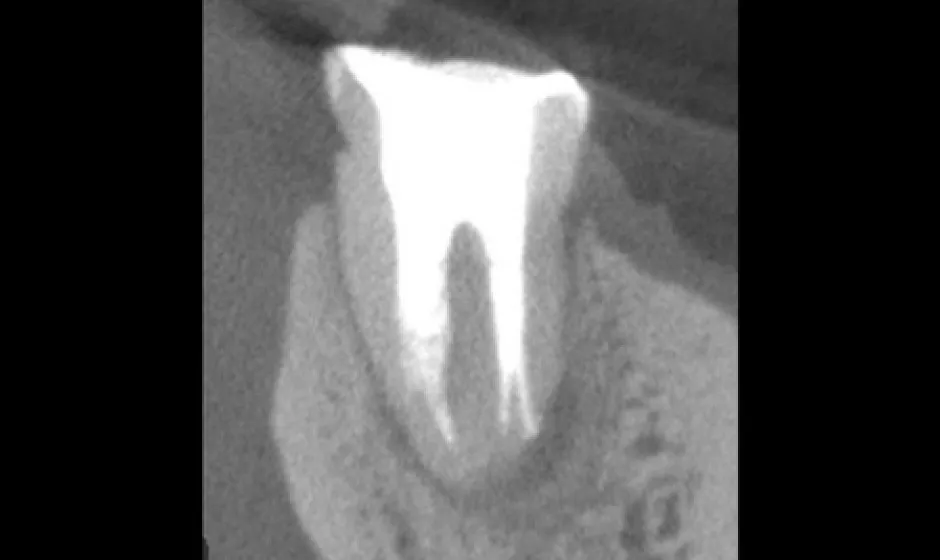

可能な限り歯を残す精密治療

できるだけ歯を守るために、削る量を抑え、神経を残せる可能性も視野に入れながら治療方針を検討します。

歯科用CTで状態を立体的に把握し、必要に応じてマイクロスコープを用いて細部まで確認しながら処置を実施。見えにくい部分ほど丁寧に対応することで、治療精度を高め、再治療のリスクをできる限り減らすことにもつなげます。 -

01精密根管治療

「抜くしかない」と言われた歯でも、根の中の感染を適切に抑えられる治療技術があれば、歯を残せる可能性があります。根管は非常に細く複雑で、わずかな取り残しが痛みや腫れの再発につながることもあるため、当院では必要に応じてCTやマイクロスコープを活用し、原因を見極めながら丁寧に処置を進めます。

医療法人大杉歯科医院が大切にしているのは、早く終える治療ではなく、歯を守る治療。津市で、できるだけ天然歯を残したい方の選択肢になれるよう取り組んでいます。症例1

症例2

- 治療名

- マイクロスコープとラバーダムを使用した精密根管治療

- 患者様

- 40代女性

- 執刀医

- Dr. 大杉

- 治療期間

- 3ヶ月

- 治療費

- 精密根管治療:130,000円(税込)

築造:40,000円(税込)

セラミック:130,000円(税込) - リスク

- 治療中〜治療後に痛みが出る場合あり

再感染・治癒不全の可能性

補綴後も定期管理が必要